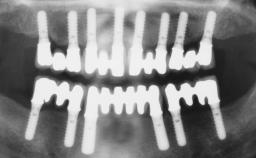

A 63-year-old female patient was referred to the University Medical Center in Groningen, Netherlands, for dental implant treatment. The patient had been edentulous in the upper jaw for 20 years. The remaining teeth in the lower jar had been removed two years before the consultation. The patient was wearing her first maxillary denture and her second mandibular denture; the latter was 1 year old at the time. The conventional upper denture had functioned satisfactorily for many years, but the patient complained about reduced stability and insufficient retention of her lower conventional denture. Her medical history revealed no significant findings. The intraoral examination revealed minor resorption of the maxillary alveolar process and extreme resorption of the mandibular alveolar process.

# of Implants | 2 |

Type of Implants | One-Piece |